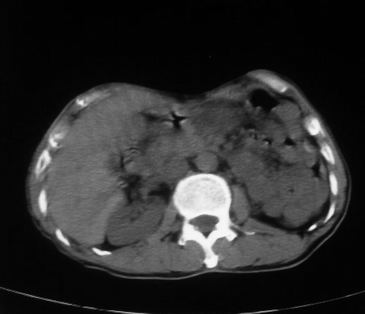

男,66岁,贲门ca术后一年,喝了5、6杯水了。怎么描述跟诊断啊